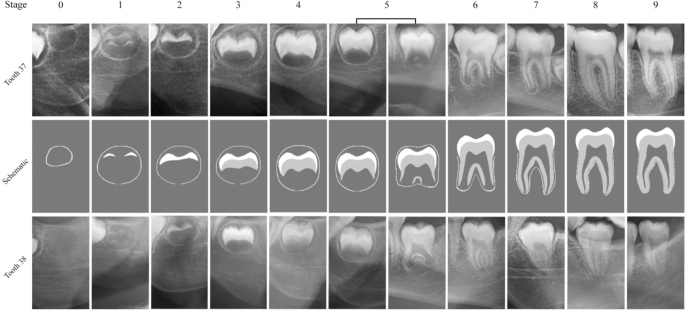

We utilise two separate datasets, one for tooth 37 and one for 38. The original OPGs were retrospectively selected from a set of 4000 OPG images collected at UZ Leuven, Belgium between 2000 and 2015, and subsequently anonymised by removing all patient information except for sex and age. Local ethics approval was obtained from the Ethical Commission Research UZ/KU Leuven (S62392), and consequently, informed consent was waived by Ethical Commission Research UZ/KU Leuven. The study was conducted in compliance with ICH-GCP guidelines, and the principles outlined in the World Medical Association Declaration of Helsinki on medical research. A primary selection pass was performed in order to exclude the records with (1) full absence of any permanent tooth type, (2) presence of orthodontic appliances, (3) bad image quality, (4) drastic overlap between any two teeth, and (5) pathologically abnormal teeth positions. The subjects were of Belgian origin within the age range of 0 to 24 years old, with a mean age of 14.56 ± 5.78. A secondary selection step resulted in 20 samples per stage, per tooth. Figure 2 shows the number of samples per stage for the two teeth. The individual teeth were then cropped out of the original images with a standardised bounding box setup using Adobe Photoshop 2021®. The cropped images were labelled into ten developmental stages three junior investigator, who were trained and calibrated at our institution, and decided in consensus on the staging. A fourth senior investigator, with 19 years of experience in dental staging for age estimation, resolved disagreements. We chose to apply an augmented Demirjian scheme, described by De Tobel et al.11. The scheme rates tooth development by assigning a stage number ranging from 0 to 9. The original Demirjian scheme ranges from stage A to stage H, with the advantage that it is based on anatomical criteria, whereas some other schemes are based on the predicted root length5. In the augmented scheme, a stage 0 is added for the crypt stage, and a stage 8 for starting apical closure (which is intermediate between Demirjian G and H). This additional stage 8 is highly relevant around the age of 18 years old, and can therefore help increase the accuracy of discerning minors from adults36. A visualization of teeth from each stage, and the diagrams for the stage criteria are shown in Fig. 3. The resulting tooth 37 dataset contained 390 tooth images (195 male, 195 female), and the tooth 38 dataset consisted of 400 images (200 male, 200 female). As for the preprocessing, all bounding box images were intensity-normalised individually, limiting the values to [0, 1] for all samples, and resized to 224 \(\times\) 224 pixels to facilitate faster model training (Supplementary Fig. 1). In order to artificially expand the training data and improve model generalization, on-the-fly data augmentation was applied during all training steps. These augmentations included random brightness and contrast jitter with a probability of 0.3, and random affine transforms for all samples which consisted of random rotation in the range \([-5^\circ , 5^\circ ]\), random translation by \([-12, 12]\) pixels in both the x-axis and the y-axis, and a random scaling by a factor of [0.8, 1.2].

Schematic representations and illustrative case examples of the developmental stages, based on the modified Demirjian staging technique. Note the subtle differences in the bounding box sizes surrounding teeth 37 and 38. Tooth 38 appears relatively smaller than tooth 37 due to the use of larger bounding boxes, which were deliberately sized to fully encompass each tooth. This approach accounts for the greater anatomical and positional variability typically observed in tooth 38 compared to tooth 37.